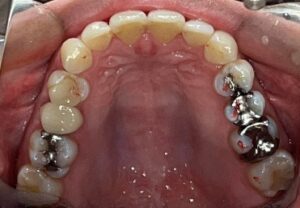

当院では、むし歯などで失ったり、削合した部分を

セラミック、ジルコニアセラミックなどで補うことが多くあります。

むし歯治療だけでなく、銀歯からの交換、歯並びや歯の形・大きさ、変色などの症状にも適しており、

本物の歯と区別がつかないような自然な見た目とかみ心地を得ることができます。

こちらはこれから実際にセット予定の色々な種類のセラミックです。

セラミックによる修復治療は当院の専門分野です。

一般的な修復治療よりも緻密な型取りと、信頼できる技工所との連携による「精密修復」をご提供します。

セラミックの材料にもいくつか種類があり、

それぞれ特徴があるため患者様のケースにあったものをチョイスしています。

こちらが実際のセット後の写真です。

上の犬歯から犬歯までの6本の歯に審美治療を行っています。

治療のタイミングが異なるため

メタルセラミック、レイヤリングジルコニア、

ジルコニアラミネートべニア(付け爪のように薄いジルコニアを張り付ける方法)

等の材料をつかっています。

スーパーセラミスト常泉氏(ホームページ参照)が丹念に製作しております。

自然で美しい仕上がりに満足いただけています。